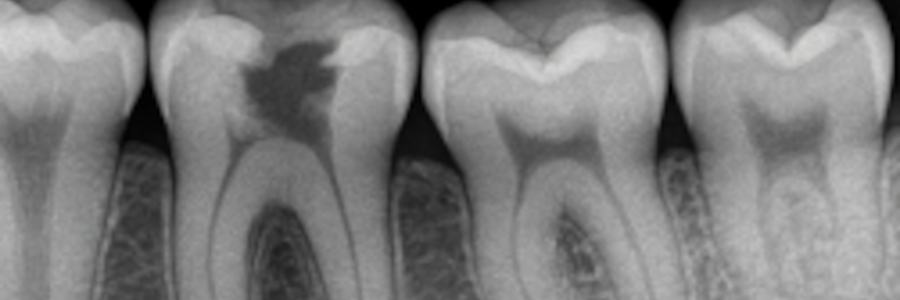

Lorsqu’une dent est abîmée, plusieurs options permettent de la restaurer: obturation en composite, facette dentaire ou couronne céramique. Le choix dépend de l’étendue de la lésion, de la quantité de dent saine restante et de l’objectif esthétique recherché.Votre dentiste à Bagneux vous explique dans quels cas chaque solution est indiquée.

La carie dentaire est le résultat d'une déminéralisation de l'émail, provoquée par les acides que rejettent les bactéries lorsqu'elles consomment des glucides.